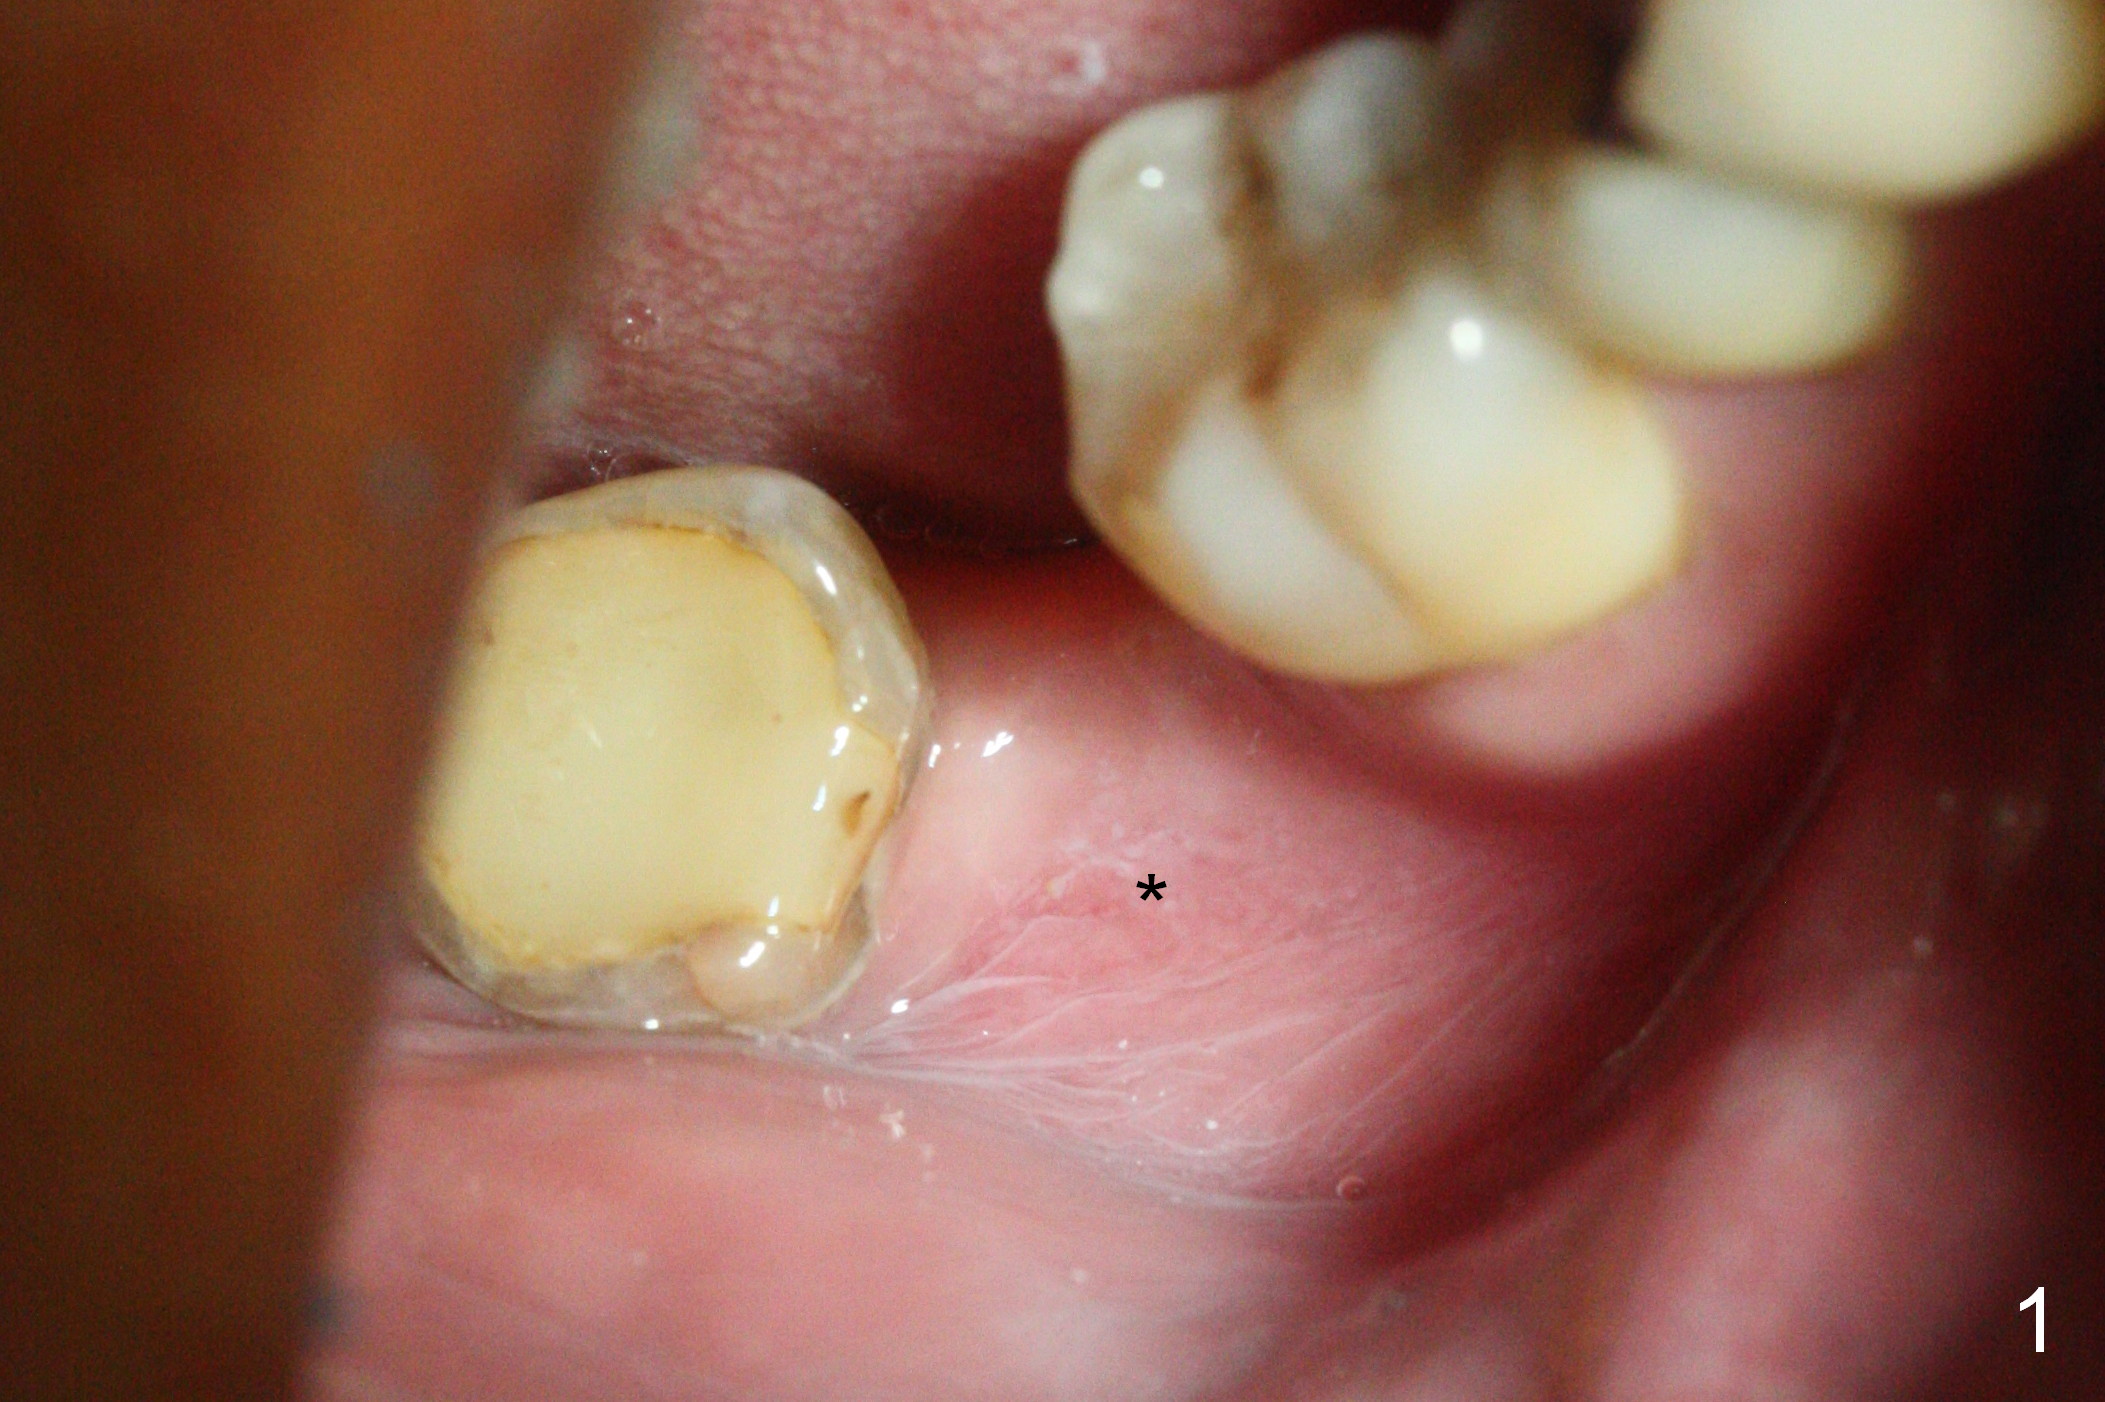

The ridge at #31 is also narrow buccolingually (Fig.1 *). After incision and 1.6 mm pilot drill, a guide pin with 7 mm length is inserted to confirm trajectory and depth; it appears that 11 mm osteotomy has enough clearance from the superior border of the Inferior Alveolar Canal (IAC, Fig.2 red dashed line). Following Marking Bur, 3.3 mm Magic Drill and final drill, the buccal plate seems to be thin (Fig.3 *). When a 4x11 mm IBS implant and 5x4(2) mm pair abutment are placed, the distal thread is exposed (Fig.4 >), the abutment contacts the opposing tooth (data not shown) and there is 2.7 mm clearance from IAC. After increasing the osteotomy 1-2 mm, the implant is placed deeper; the autogenous bone with Osteogen is placed around the plateau of the implant (Fig.5 >), particularly buccally, followed by collagen membrane. When sutures are placed around the abutment, the buccal ridge looks bulkier (Fig.6) than preop (Fig.1). It may remains so long term. The flap surgery makes it possible for simultaneous GBR and reduction in possibility of peri-implantitis. Last, periodontal dressing is applied.